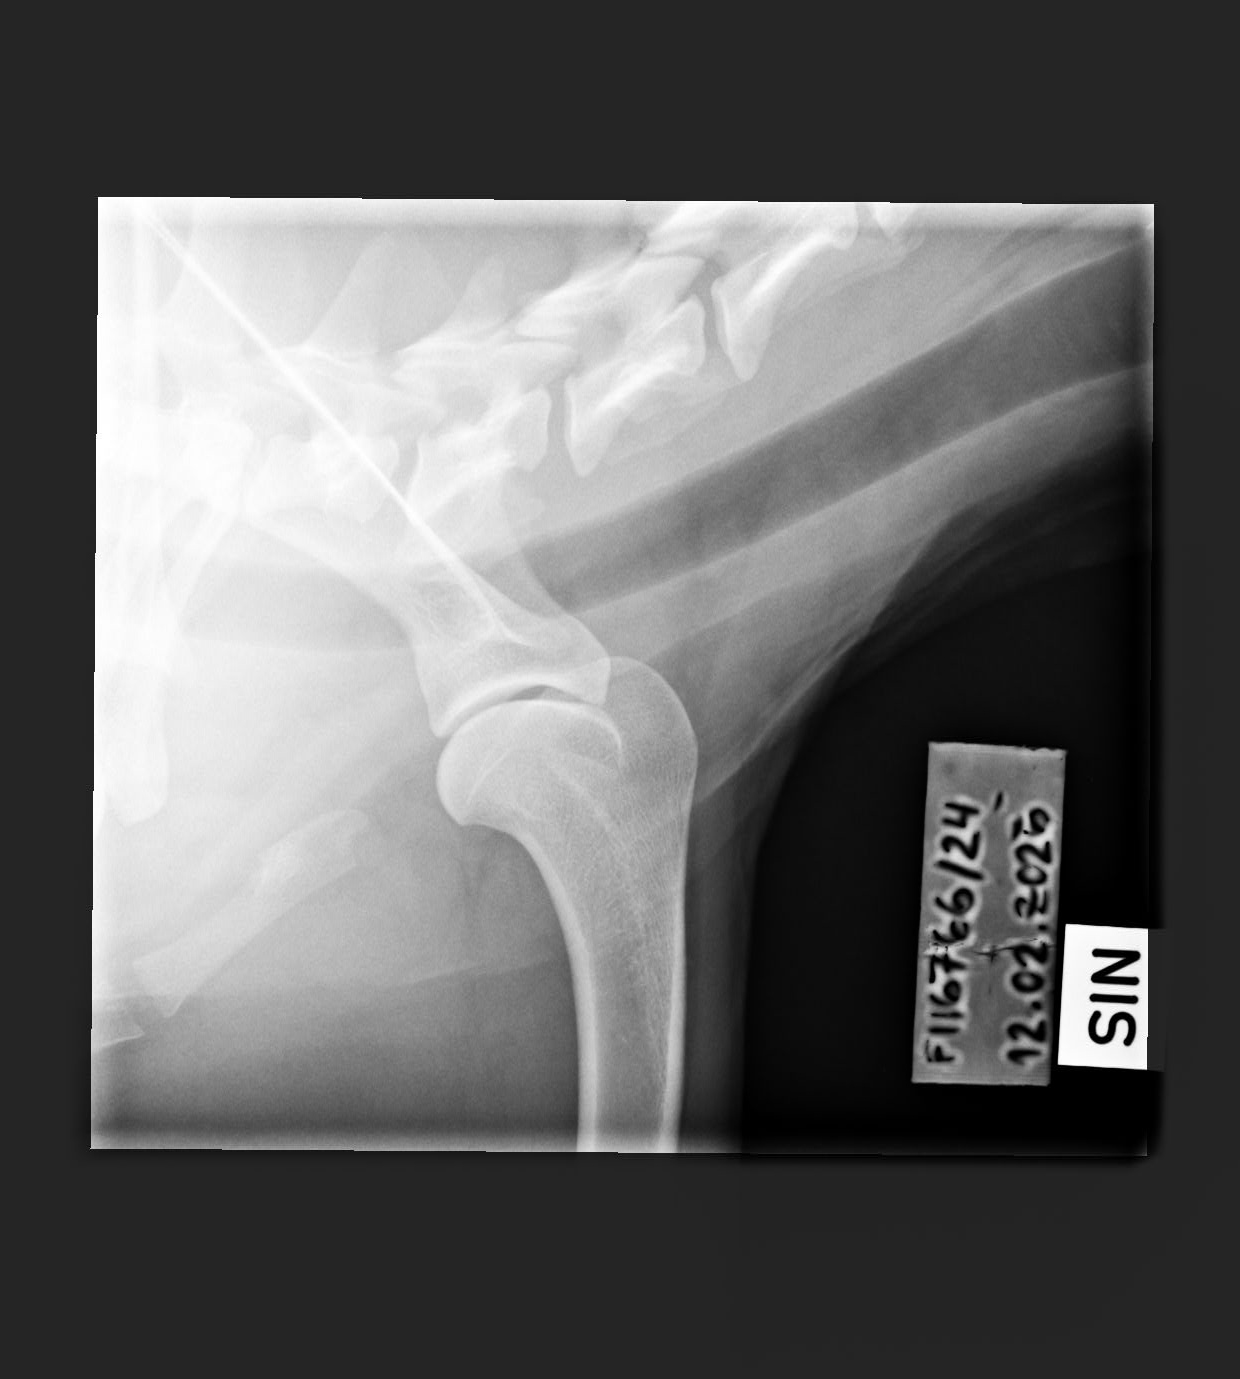

- Shoulder osteochondritis: Unaffected/Unaffected